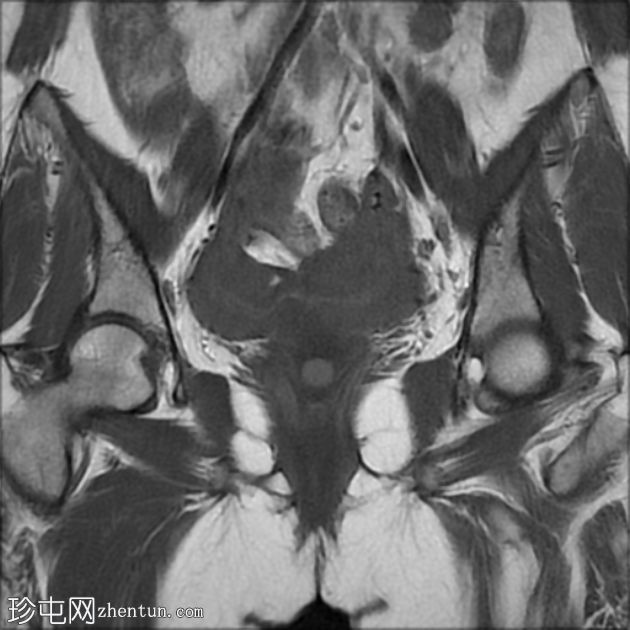

冠状位

T2加权像

双角子宫,有两个子宫角和一个宫颈(单颈双角子宫)

右角正常,分区解剖结构正常,无肌层病变

左角局灶性前壁腺肌症,前壁交界区边界不清,肌层内可见多个高信号灶

两个小的间质性肌瘤和一个大的浆膜下肌瘤

该病例表现为双角子宫单宫颈(双角单颈子宫),左侧单侧局灶性子宫角腺肌症,以及多发性子宫肌瘤。